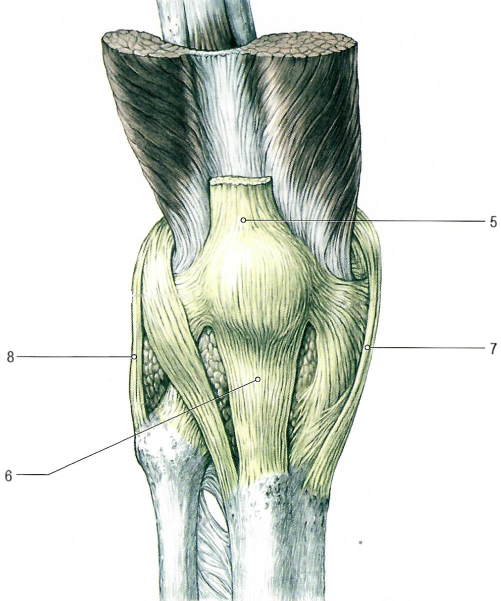

Коленный сустав по строению сложный, комплексный, по форме мыщелковый, по функции двуосный.

Сустав образован мыщелками и надколенниковой поверхностью бедра, верхней поверхностью большеберцовой кости, суставной поверхностью надколенника (имеет медиальный[2] и латеральный[1] мениски).

В суставе возможны сгибание и разгибание голени, вращение (при полусогнутом положении голени).

Связки, укрепляющие коленный сустав.